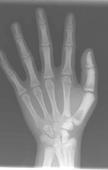

骨硬化病即石骨症(osteopetrosis),又称大理石骨病,其特点是全身性骨质硬化,骨塑型异常,进行性贫血,肝脾肿大,容易骨折,往往有家族史。

- 常见症状:面色苍白、 眼距宽阔、 儿童反复骨折前囟饱满、 脊柱侧弯 、髋内翻耳聋、 脑积水 、贫血、 视神经萎缩 、方颅、前囟饱满、眼距宽、失明、骨折、